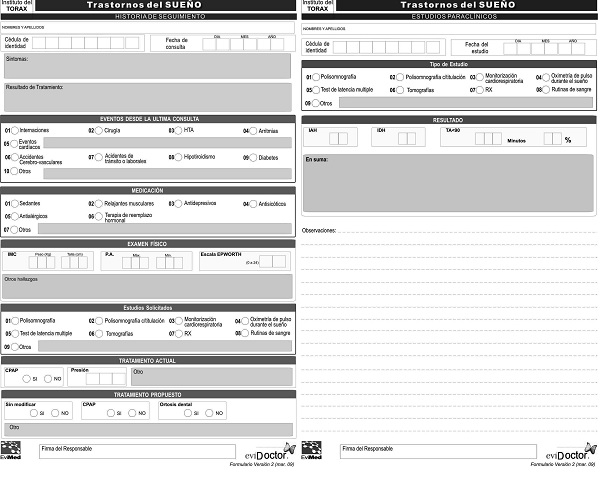

Se revisaron los registros de 3109 pacientes, (2279 del sistema mutual y 830 del Hospital de Clínicas), del período comprendido entre 1990 y 2014. En un subgrupo de pacientes con apneas del sueño (n = 447), se aplicó una historia clínica electrónica (HCE), desarrollada para este fin por Evimed (www.evimed.net, Apéndice 1), que permitió el relevamiento de casos desde 2010 a 2014. Este conjunto fue usado para relacionar los resultados de la anamnesis y el examen físico con datos fisiológicos. Para la evaluación cuantitativa de los síntomas y el impacto de la calidad del sueño en múltiples actividades de la vida diaria se aplicaron la escala de somnolencia de Epworth5 y el cuestionario de resultados funcionales del sueño FOSQ6.

Las modalidades de estudios del sueño utilizadas7)(8)(9)(10)(11 incluyeron: polisomnografía atendida por técnico en laboratorio del sueño (nivel 1) en sus modalidades de noche completa y noche dividida, en 2891 casos (93%). En el sistema mutual exclusivamente, a partir del año 2012 se utilizaron polisomnografía portátil del sueño (nivel 2) ó poligrafía respiratoria durante el sueño (nivel 3) en 183 casos (5.9%) y oximetría de pulso durante el sueño (nivel 4) en 35 casos (1.1%).

La polisomnografía incluyó registro simultáneo de: video con luz infrarroja, posición corporal, electroencefalograma, electrooculograma, electromiograma mentoniano y de miembros, micrófono en el cuello, electrocardiograma, flujo aéreo nasal y bucal (termistor), flujo nasal (presión), movimientos respiratorios abdominales y torácicos (sensor piezoeléctrico) y saturación de oxígeno del pulso. La estadificación del sueño se realizó en forma manual mediante lectura del registro diferida, siguiendo criterios estandarizados de Rechtschaffen y Kales12. A partir de 2007 se usó la actualización de la estadificación de la AASM13. Para la clasificación de los diagnósticos se utilizó la Clasificación Internacional de Trastornos del Sueño14.

Los instrumentos utilizados fueron: polígrafos Grass 49, ATI Delphos, Akonic, Copumedics Somte y Apnea Link; oxímetros Criticare 504 y NonIn.